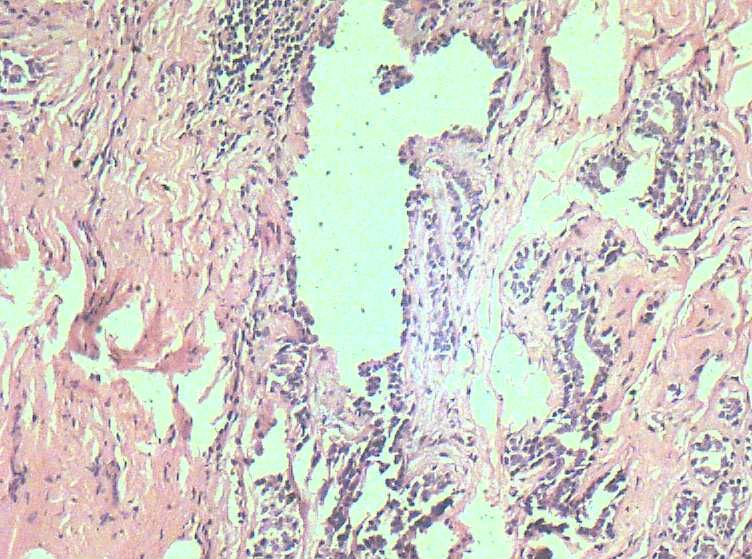

B3774乳腺积乳性包块?

女41岁,左腺包块。肉眼:不整形囊壁样组织,大小2*1.6*0.3CM,壁厚0.1—0.3,未触及结节,未见出血及坏死。

标签:乳腺纤维囊性增生症

似乎有导管扩张、慢性炎细胞浸润、大汗腺化生、普通型导管增生等病变,没有看到囊壁内衬上皮或囊壁结构。

。图12-16可以看到导管上皮异形增生(导管上皮极向紊乱)